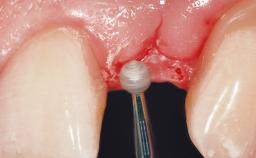

Surgical treatment of a 67-year-old male patient exhibiting an extended edentulous space in the anterior maxilla after the removal of three hopeless incisor teeth.

The video demonstrates implant placement using a surgical stent according to the principle of prosthodontically driven implant placement. The deficient ridge is augmented with locally harvested autologous bone chips, a superficial layer of xenogenic DBBM particles and a resorbable collagen membrane. The surgery is completed with a precise, tension-free primary wound closure.

Bone Augmentation Horizontal|Simultaneous

Augmentation Materials Autogenous chips|Xenogenous|Membrane

Bone Volume Deficient horizontally, allowing simultaneous augumentation